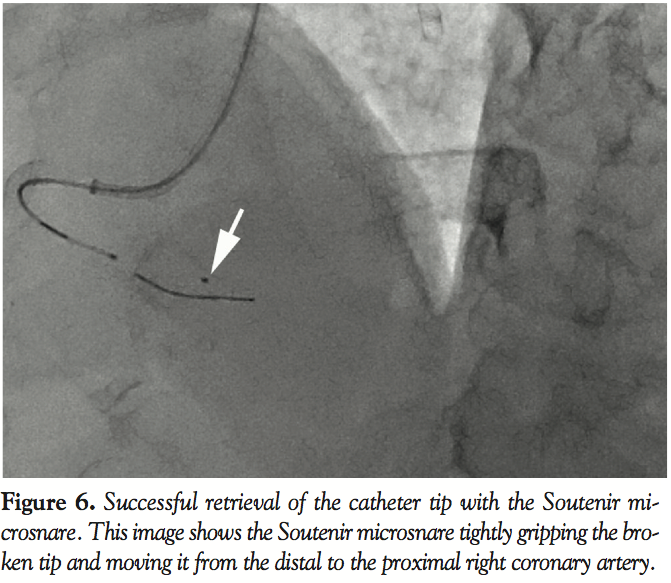

We then used a filter device that passed through the broken tip and succeeded in returning it to the middle of the RCA; however, the filter was unable to remove the tip out of the artery because it had entered the space on a side of the broken tip. Hence, although the filter reached the tip, it could not capture it (Figure 5). Thus, we selected the Soutenir device to remove the tip. First, the microcatheter, which had a 0.020˝ lumen, advanced into the AV branch with the conventional guidewire. The Soutenir easily passed through the microcatheter and reached the distal AV branch. The Soutenir basket remained in the microcatheter during its advancement through the RCA; however, on reaching the distal AV branch, the basket protruded out from the microcatheter. Using the basket, we very gently pulled the Soutenir microsnare out of the right ventricular branch. It had successfully captured the broken catheter tip, and the snare along with the retrieved catheter tip was easily drawn out through the guide catheter (Figures 6 and 7). A final angiogram showed that the procedure caused no injury to the distal RCA (Figure 8).